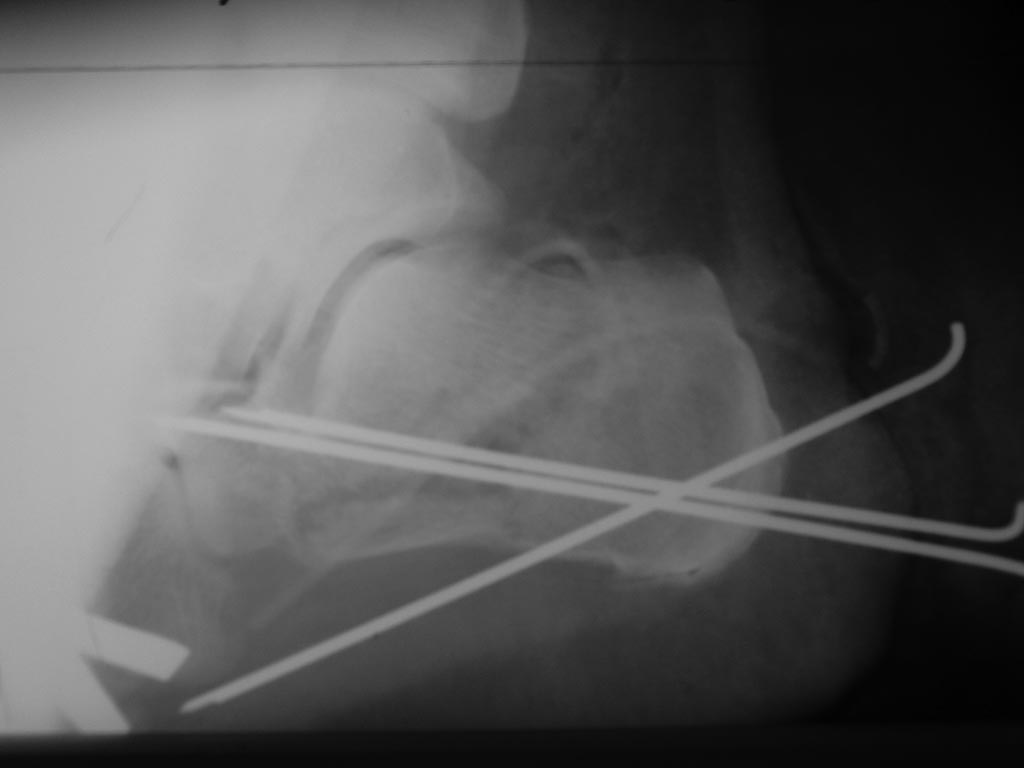

Пациента прооперировал 5 мая. Произвел аутопластику костной крошкой и фиксацию спицами. Выкладываю снимки